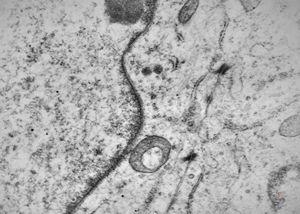

M,50y. | Pneumocystis carinii - lung